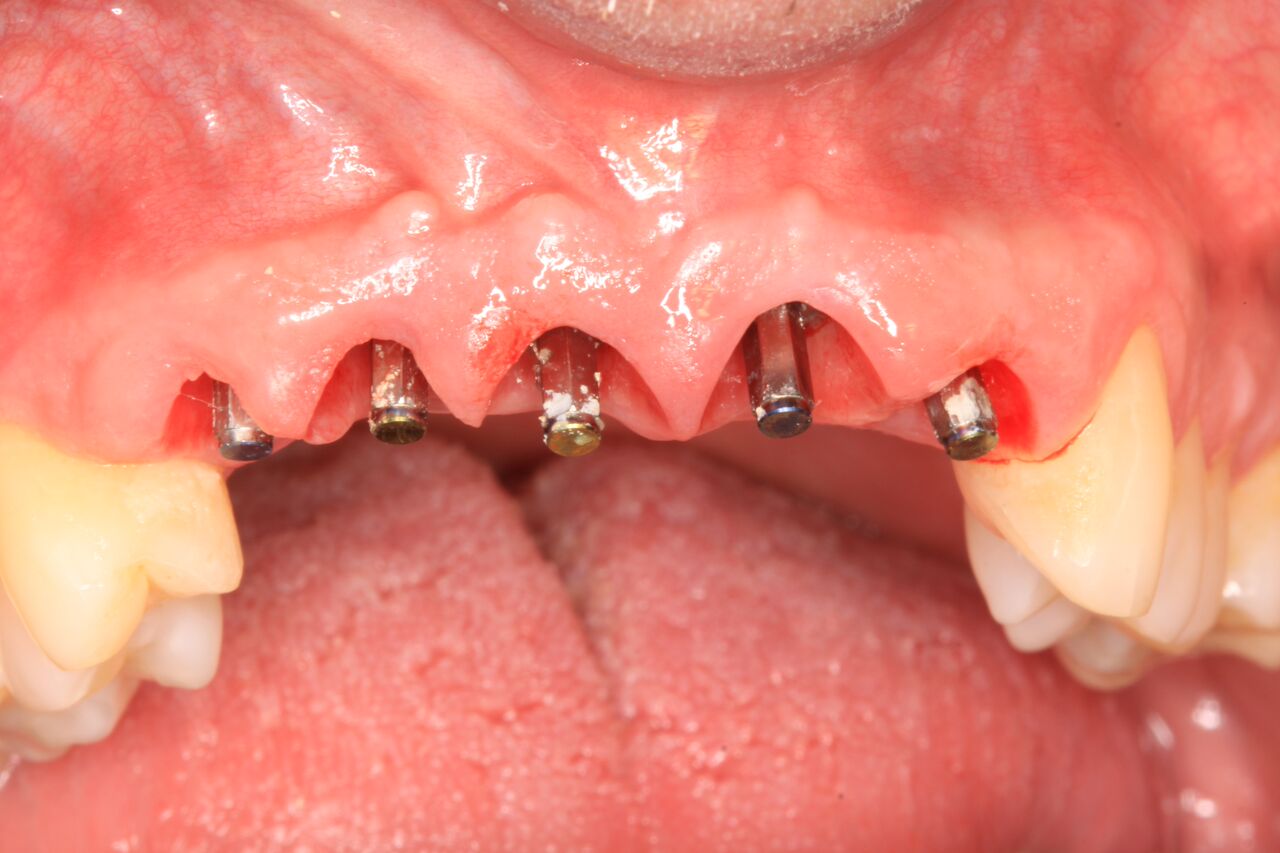

(20.) 6-month integration confirmation of Nos. 6 through 10.

Figure 20

(21.) 6-month integration confirmation of Nos. 6 through 10.

Figure 21

A 42-year-old man presented with a very loose bridge on Nos. 6 through 9 with periodontally compromised retainers on Nos. 6 and 9 (Figure 17 through Figure 19), and endodontically involved No. 10 with a calcified canal. Teeth Nos. 6, 9, and 10 were extracted, the sockets fully debrided, and pontic soft tissue on Nos. 7 and 8 sculpted to be symmetrical in soft tissue contour with the contralateral lateral incisor and central incisor locations. Implants were secured in position Nos. 6 through 10 (Figure 20) in excess of 45 Ncm, the bone was milled to provide unimpeded seating of temporary abutments, and temporary crowns were fabricated chairside and adjusted to be out of occlusion in centric relation and all excursions. The temporary crowns were cemented after extrusion of excess cement extraorally and the patient was prescribed antibiotics, analgesics, and instructed in postoperative care particular to immediately provisionally restored implants. At 6 months, integration was confirmed (Figure 20 through Figure 23) and after placement of scanning abutments, the implants and soft tissues were scanned. Final crowns were fabricated from the scanned images and were cemented after extrusion of excess cement extraorally (Figure 24 through Figure 26), and oral hygiene procedures were reviewed.